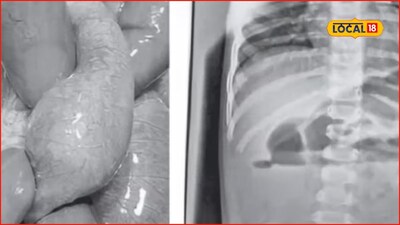

- •Gabriel Golden was born at just 22 weeks gestation, weighing a mere 450 grams, with hands as thin as pencils.

- •Gabriel spent a year in the NICU, battling 'Chronic Lung Disease' and multiple pneumonias, requiring a tracheostomy.